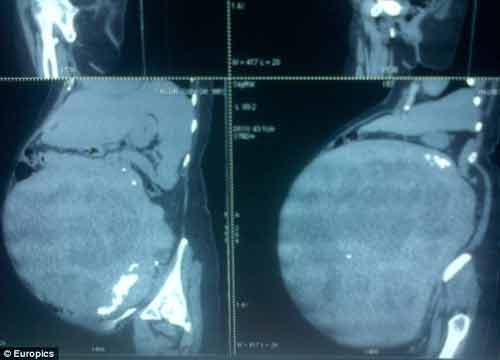

| Hình chụp X-quang bụng bà Latha. |

Chưa đầy 2 ngày sau khi nhập viện, người phụ nữ đã được tiến hành phẫu thuật cắt bỏ khối u lớn trong bụng. Khối u này có trọng lượng 15,6kg và đường kính lên tới 53cm.